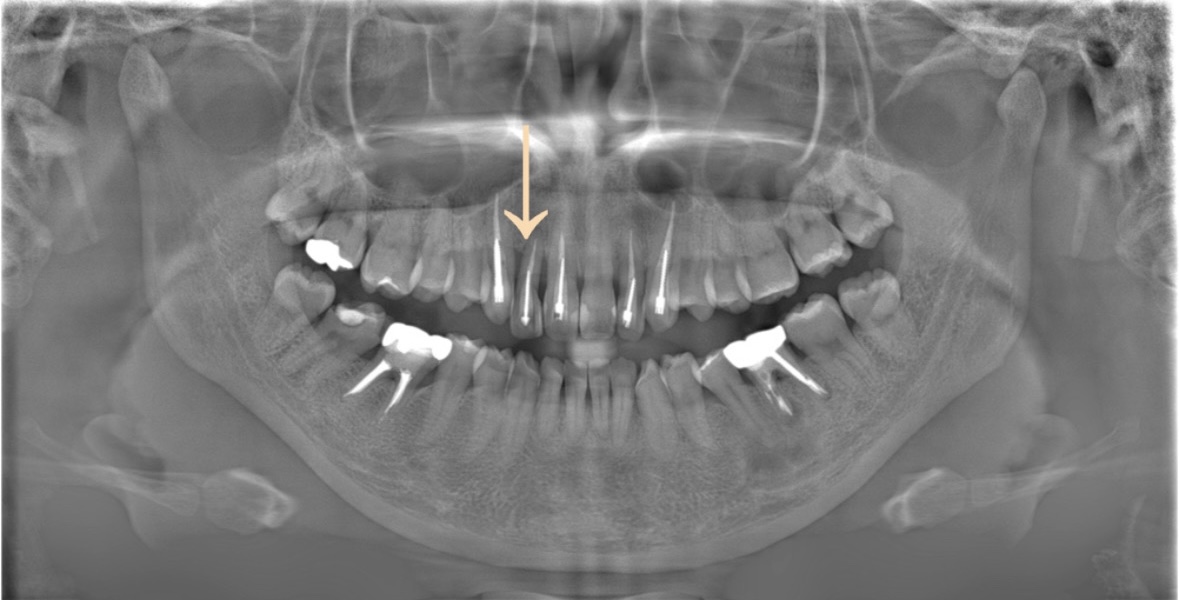

例えばこのような状態の方です。

この様に、骨の吸収が歯の周り全体的に進行している場合は歯を支える力がない為、歯を残す事が困難です。

それでは、どの様な状態の方が歯周再生療法が適応なのか、実際に行った患者様のレントゲン写真で説明します。

白色の矢印が骨の位置を示しています。

[初診時]

垂直的に骨がなくなっている状態。ここに骨を再生する薬剤を入れて骨を作る処置をします。

[歯周組織再生療法後(外科処置の1年後)]

骨の高さ・角度が変わった事がご理解いただけますでしょうか。

この方は、全ての処置が完了した後、

定期的なプロケア+メインテナンスに通っておられる為、現在も良い状態で維持されております。

部分的(垂直的)な骨の吸収の場合でしたので、今回の治療が適応でしたが、全体的に骨の吸収がある場合は抜歯になる事もございます。